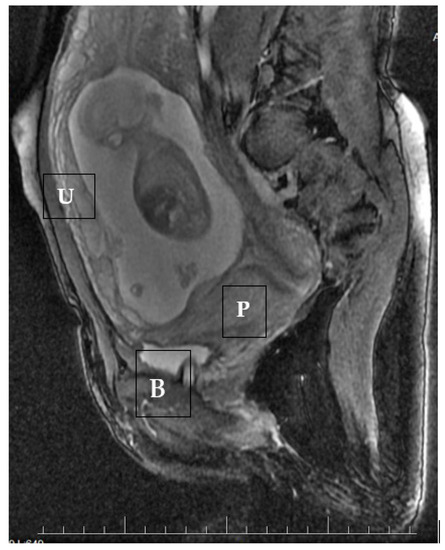

- the detection of a gestational sac within the anterior lower segment of the uterus embedded in the cesarean scar,

- an absent or thin (<5 mm) myometrium layer between the gestational sac and the bladder,